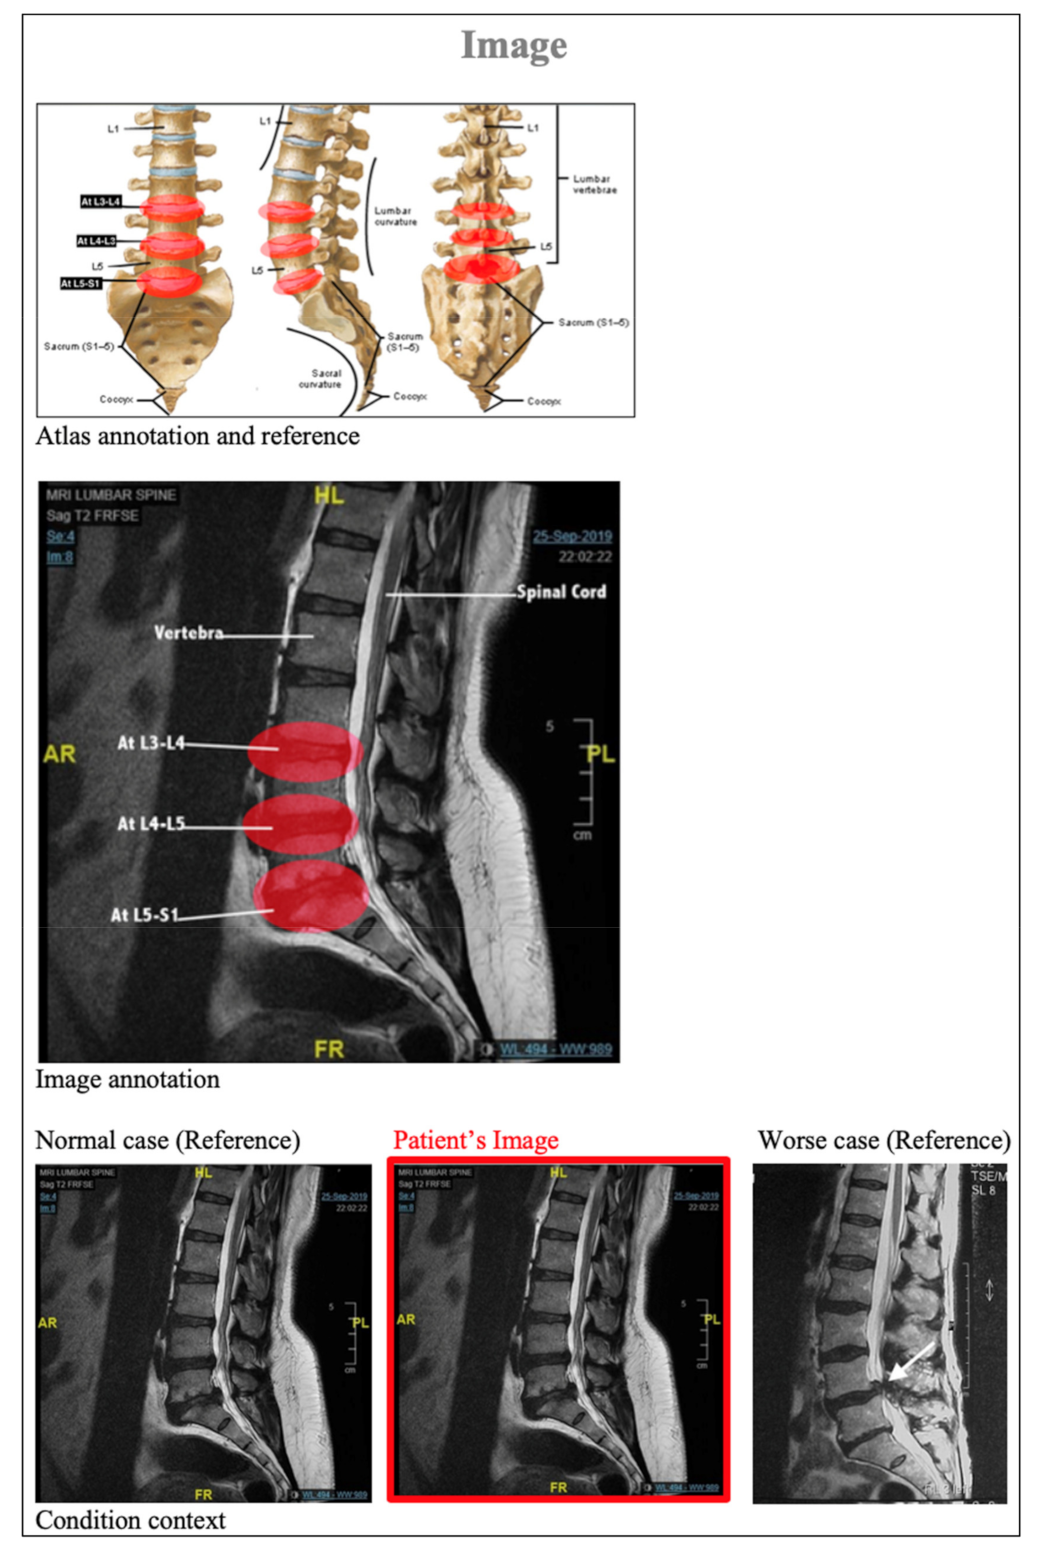

| 2. | According to the report (image and notes), can you determine the location of the issues? | a. At L3 L4 b. At L4 L5 and L5 S1 c. At L3 L4, L4 L5, and L5 S1 d. I do not know | 1 |

| 3. | According to the report (Image), can you determine the location of the L5 S1 in the following image![]() | a. A b. B c. C d. I do not know | 1 |